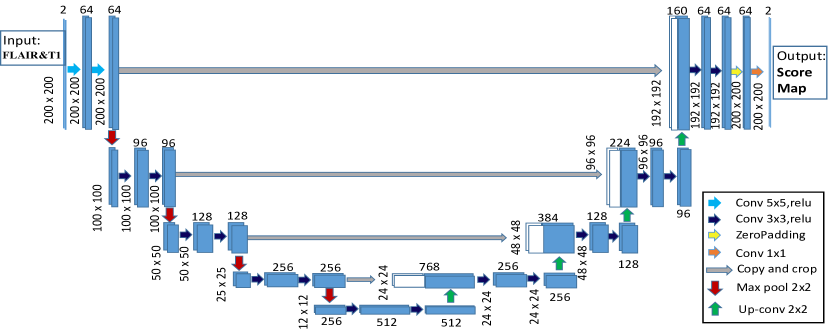

3.2 Fully Convolutional Network

3.2.1 2-D Convolutional Network Architecture

Convolutional neural network has proven to be an effective computational model for automatically extracting image features. Recently the fully convolutional networks (FCN) (Long et al., 2015) and their its extensions (Milletari et al., 2016) have been used for medical images segmentation. We build a variant of FCN architecture based on U-Net (Ronneberger et al., 2015), which takes as input the axial slices of two modalities from the brain MR scans during both training and testing. Our network is shown in Figure 4. For each patient, the FLAIR and T1 modalities are fed into the U-Net jointly as a two-channel input. It consists of a down-convolutional part that shrinks the spatial dimensions (left side), and up-convolutional part that expands the score maps (right side). The skip connections between down-convolutional and up-convolutional were employed.

In this model, two convolutional layers are repeatedly employed, each followed by a rectified linear unit (ReLU) and a 22 max pooling operation with stride 2 for downsampling. At the final layer a 11 convolution is used to map each 64-component feature vector to two classes. In total the network contains 19 convolutional layers. Convolutional layers with kernel size are heavily used in our model. Different from the basic architecture of the recent work (Ronneberger et al., 2015), for the first two convolutional layers, kernel size is replaced with size in order to handle different transformations. This is motivated by a recent study (Peng et al., 2017) suggesting that large kernel size should be adopted in the network architecture. This step could enable dense connections between feature maps and per-pixel classifiers, enhancing the capability of a network to handle different transformations.